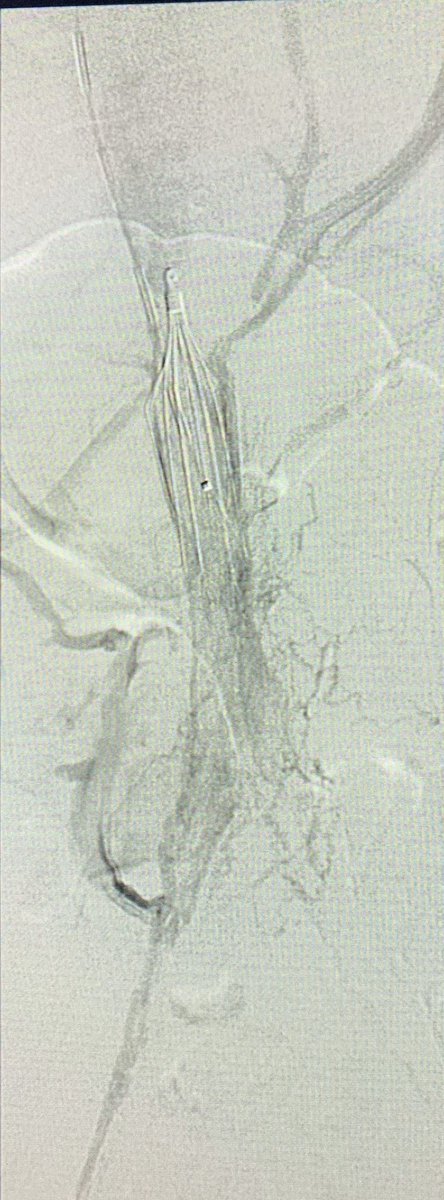

56 Y O known Chronic Liver Disease with Isolated Gastric Varices. Treated by

#Balloon#Occlusion Transvenous#Obliteration and#VascularPlug Placement#Intervention#Radiology#Makkahpic.twitter.com/0eup4cuY7x